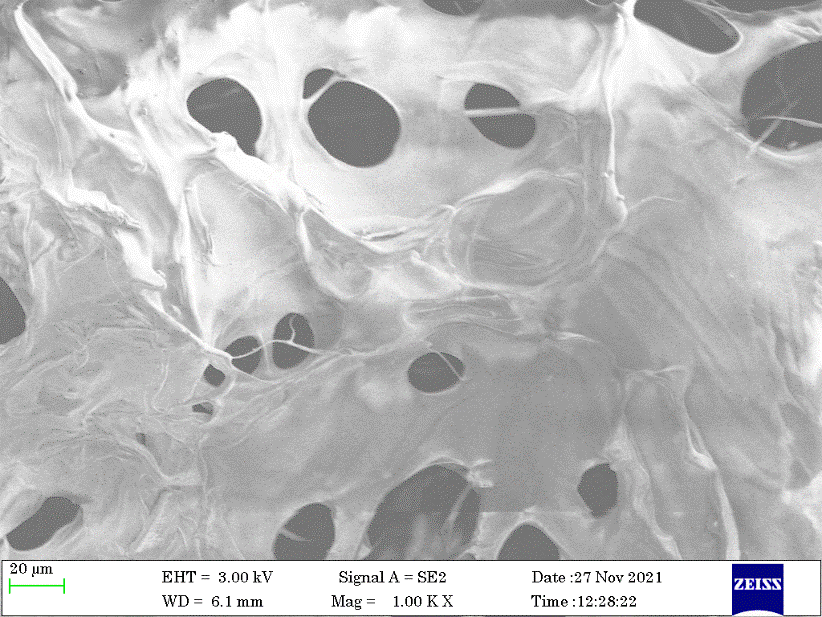

Matrix morphology

For cell penetration and multiplication, the right pore size was necessary. A crucial component for the exchange of gas, waste, and nutrients for cells inside the scaffolds, all of the samples included diverse and linked open pores. Using Image J software, the SEM images (fig. 6-8) were processed, and the results showed that the sample's pore size ranged from 105 µm to 188 µm. Table 2 lists the scaffolds minimum and maximum pore diameters. Due to the increased concentration of chitosan in formulation CG31-A, the pore size was the biggest at 188 µm, which is consistent with the study done by Azizian et al. (2018) [13]. The hydrophilic nature of chitosan and gelatin, which encourages the absorption of higher water contents and results in the creation of larger ice crystals that were evaporated during the lyophilization process and observed as pores, may also be the reason why all the scaffolds have larger pores.

Fig. 6: SEM of CG31

Fig. 7: SEM of CG11

Fig. 8: SEM of CG13